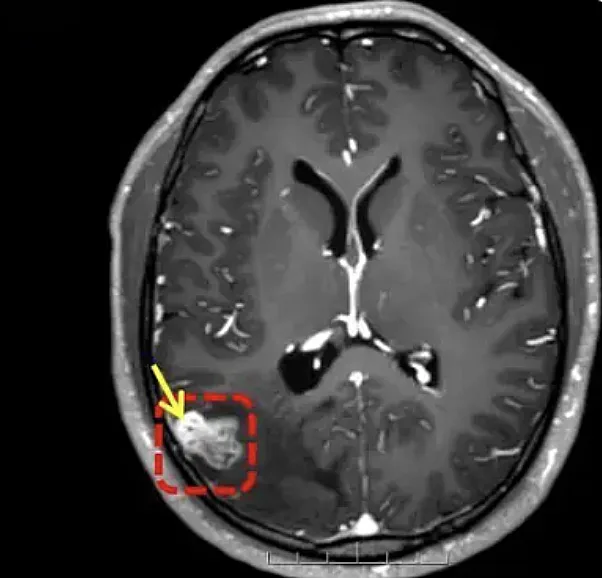

עם זאת, בבדיקת MRI שנערכה באפריל 2024 נמצא במוחו גוף זר. בשלב זה לא היה ברור אם מדובר בטפיל חי או בממצא חריג אחר, אך האיש החליט שלא לעבור ניתוח והמשיך בשגרת חייו.

כשנה לאחר מכן האיש חווה החמרה פתאומית במצבו. הוא סבל מהתכהות ראייה, הקאות, קצף לבן ועוויתות חזקות בגוף. הוא פונה מיד לבית החולים, שם התברר כי במוחו התפתחה תולעת טפילית באורך 18 ס"מ.

הרופאים ביצעו ניתוח מוח פתוח להוצאת הטפיל. לאחר עשרה ימים של טיפול והשגחה, שוחרר האיש במצב יציב.